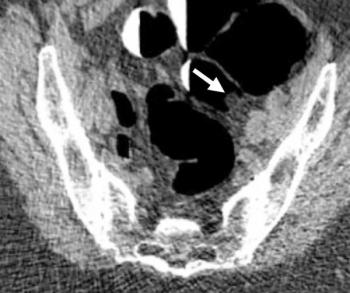

Computed tomography colonography (CTC) demonstrated a 91.6 percent positive predictive value (PPV) for polyps > 6 mm, according to new research involving over 9,000 patients who underwent CTC for primary asymptomatic colorectal cancer screening.